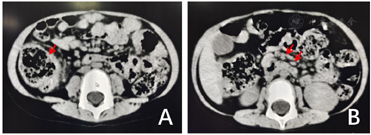

辅助检查:入院查血常规,白细胞计数14.84×109/L,血红蛋白86 g/L,血小板计数396×109/L,中性粒细胞百分比57.2%,淋巴细胞百分比31.1%;C反应蛋白166.68 mg/L,红细胞沉降率53 mm/h,降钙素原4.07 ng/ml,血尿便细菌培养、血生化、凝血功能、血尿便培养均阴性,脑脊液化验、EB病毒、巨细胞病毒检测、骨髓涂片及培养、风湿因子、自身抗体谱、结核菌素T细胞检测均为阴性,腹部彩超无明显异常。全腹部CT:1.右下腹网膜增厚,邻近肠管扩张;2.中下腹肠系膜淋巴结明显增多,部分肿大,部分沿肠系膜上动脉周围分布走行(图2)。